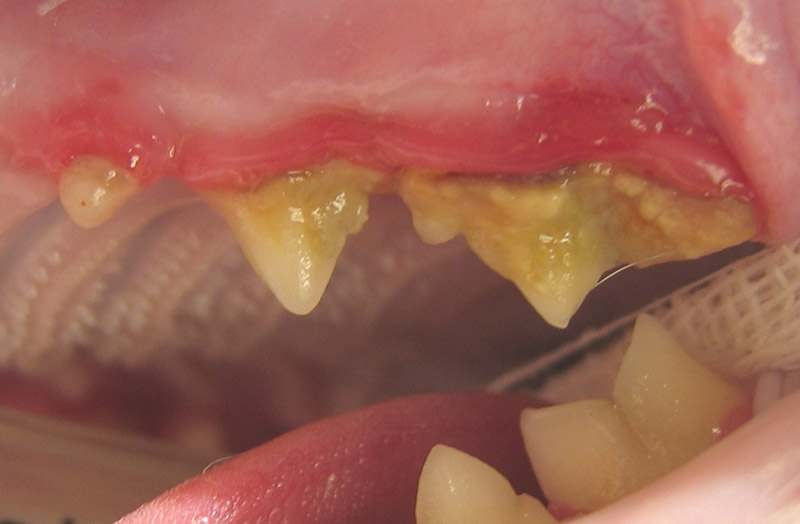

Pētījumi liecina, ka “periodontālā slimība” — kolektīvs termins, kas apzīmē vairākus mutes dobuma iekaisuma stāvokļus — sastopams 70% kaķu no trīs gadu vecuma*. Jūs, iespējams, pat nenojaušat, ka kaut kas nav kārtībā, jo simptomus var būt grūti noteikt, bet neārstēšanas gadījumā iesaistītās baktērijas var ietekmēt citas kaķa ķermeņa daļas, kā arī izraisīt sāpīgus bojājumus kaķa mutē. Tas nozīmē, ka kaķa mutes dobuma kopšanai jābūt svarīgai jūsu profilaktiskā režīma sastāvdaļai. Par laimi, ir dažas vienkāršas darbības, ko varat veikt, lai palīdzētu uzturēt kaķa mutes dobumu veselu un tādējādi pasargātu viņu no potenciāli liela diskomforta un sāpēm. Lai uzzinātu vairāk, jautājiet savam veterinārārstam vai veterinārārsta asistentam.